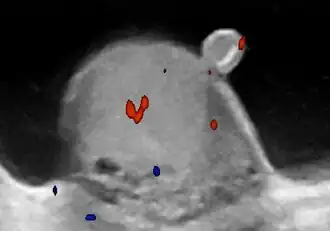

De appendix testis kan soms getordeerd raken, wat acute eenzijdige pijn aan de teelbal veroorzaakt. Een derde van de patiënten heeft een voelbare "blauwe stip"-verkleuring op het scrotum. Dit is bijna diagnostisch voor deze aandoening. Torsie van de appendix testis treedt op in de leeftijd van 0 tot 15 jaar, met een gemiddelde bij 10 jaar.[1] Bij draaiing van de appendix testis kan de zaadstreng soms worden afgekneld. Dit wordt torsio testis genoemd.